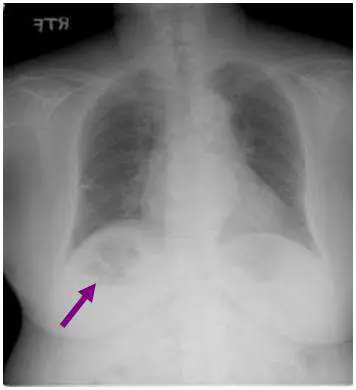

一中年女性因發燒及腹痛至醫院掛急診並 接受 X 光檢查 ,下列中何者為 箭號所示最可能的診斷:

本題考察胸腹部 X 光片對肝膿瘍(hepatic abscess)的影像判讀能力。中年女性出現發燒與腹痛,是肝膿瘍的典型臨床表現,搭配影像所見可做出診斷。

本張為胸腹部正面 X 光片(PA chest/abdominal radiograph)。箭號指向右上腹(右季肋區)一個圓形、邊界相對清晰的病灶,病灶位於右側橫膈膜下方(subphrenic region)、對應肝臟投影區域。可見該病灶呈現氣液面(air-fluid level)特徵——氣體(低密度)浮於液體(較高密度)之上,形成水平分界線,提示病灶內有產氣菌或壞死液化伴氣體積聚,此為肝膿瘍的特徵性 X 光表現之一。此外,右側橫膈膜有輕度抬高,符合肝臟病灶壓迫或橫膈膜刺激的間接徵象。病灶位置與肺部不符(未見肺實質中央性透亮腔),可排除肺膿瘍。

(A) 肺膿瘍 肺膿瘍(lung abscess)的 X 光表現為肺實質內的透亮空洞,伴有氣液面,位於肺葉內(常見右下葉)。本題箭號所指病灶位於橫膈膜下方的肝臟區域,並非肺實質內,故不符。

(B) 肝腫瘤 肝腫瘤(hepatic tumor)在 X 光片上通常僅呈現肝臟輪廓增大或鈣化,不會出現氣液面。本題病灶有明顯氣液面,不符合腫瘤表現。

(C) 肝膿瘍 ✅ 正確答案 肝膿瘍(hepatic